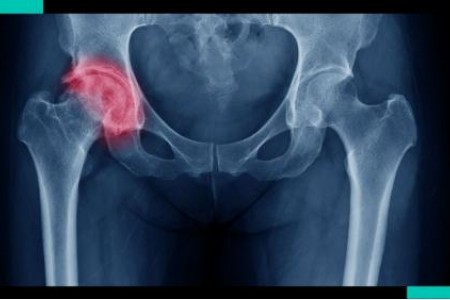

Рентгенова снимка на пациент с коксартроза 1 степен разкрива леко изразени промени: умерено неравномерно стесняване на ставната цепка, както и костни израстъци около външния или вътрешния ръб на ацетабулума при липса на промени в главата и шията. бедрената кост.

Рентгеновите снимки на коксартроза 2 степен разкриват значително неравномерно стесняване на ставната цепка (повече от половината от нормалната височина). Главата на бедрената кост се измества леко нагоре, деформира се и се увеличава по размер, а контурите й стават неравномерни. Костните израстъци с тази степен на коксартроза се появяват не само на вътрешния, но и на външния ръб на ацетабулума и се простират отвъд хрущялната устна.

❌При коксартроза 3 степен болката става постоянна и тревожи пациентите не само през деня, но и през нощта. Ходенето е трудно, когато се движи, пациентът с коксартроза е принуден да използва бастун. Обхватът на движение в ставата е рязко ограничен, мускулите на седалището, бедрото и подбедрицата са атрофирани. Слабостта на тазобедрените абдуктори предизвиква отклонение на таза във фронталната равнина и скъсяване на крайника от засегнатата страна. За да компенсира полученото скъсяване, пациент с коксартроза при ходене накланя торса си към болезнената страна. Поради това центърът на тежестта се измества и натоварването на засегнатата става рязко се увеличава. Рентгенографията на коксартроза степен 3 разкрива рязко стесняване на ставната цепка, изразено разширение на главата на бедрената кост и множество костни израстъци.